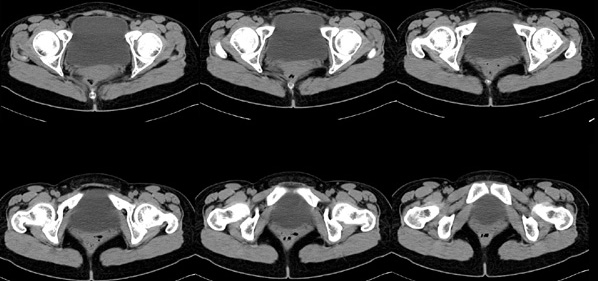

女性,28岁,停经3月,腹部膨隆1月,产前检查发现腹部占位

{肿块中心ct值27hu,增强后,动脉期、门脉期均无明显强化)

患者手术病理:腹腔囊性淋巴管瘤,象这样充满整个腹腔的的确很少见